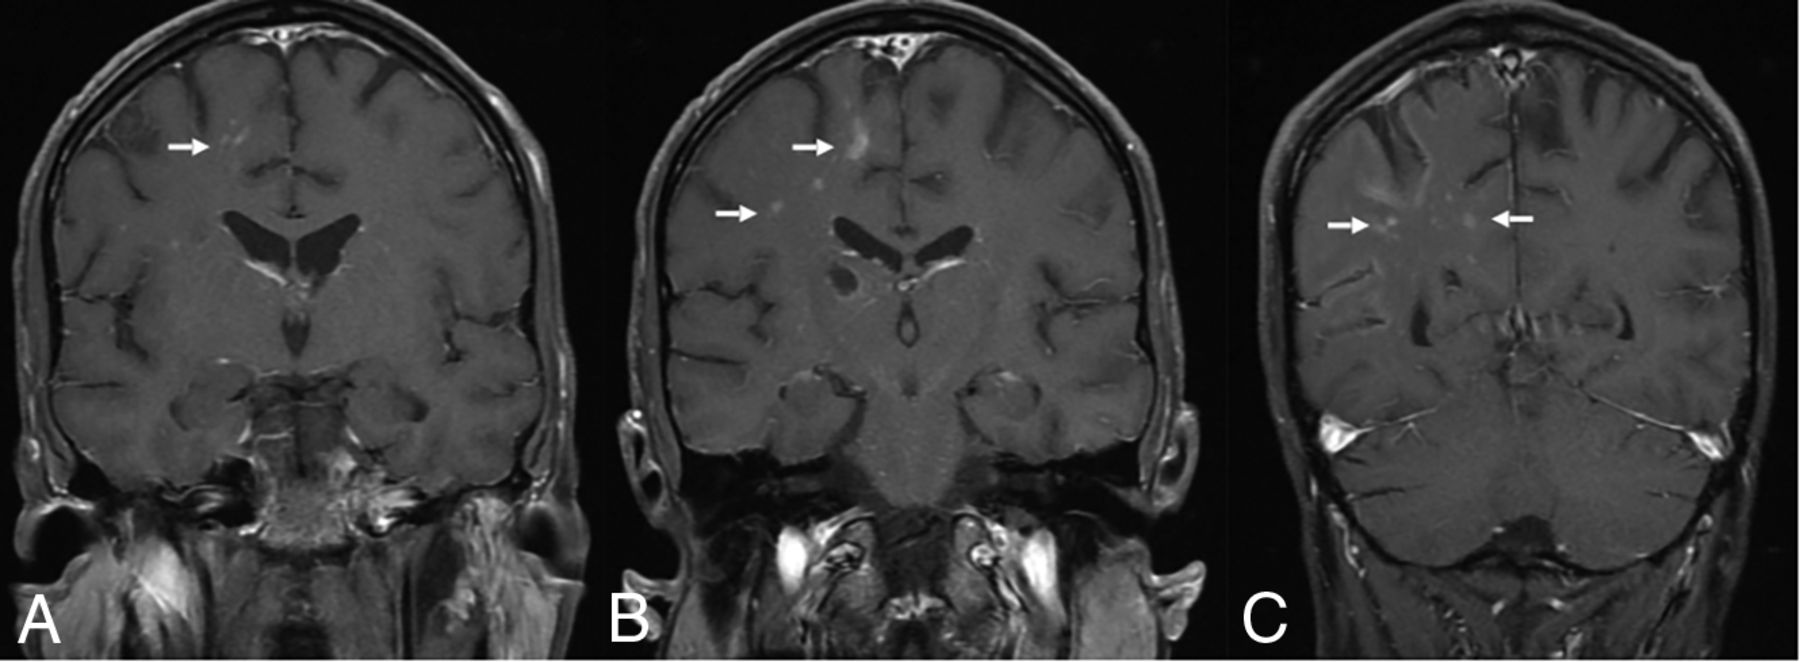

EBV is a rare cause of encephalitis in children and immuno-competent adults. The most common presentations are fever (81%), headache (66%), and seizure (10%).11 MR imaging is preferred for suspected encephalitis, with abnormalities found in 27.6%–80% of patients (Fig 1). Vyas et al12 reported abnormal findings on brain imaging in 29/45 (64.5%) pediatric patients. Cortical/subcortical (20%), white matter (15.5%), and basal ganglia (11%) involvement were more common, followed by the thalamus (9%), brainstem (6.2%), substantia nigra (4.4%), cerebellum (4.4%), and spinal cord (3%). Diffusion restriction and susceptibility changes were seen in 24.4% and 15.5% of cases, respectively. Meningeal involvement was reported in 5%–22%.9,12 Brain abscess, subdural effusion/empyema, and hemorrhage are rare.12

EBV meningoencephalitis in a patient with infectious mononucleosis. CSF was positive for EBV. Axial T2 FLAIR (A and B) images show multifocal areas of hyperintensity mainly within the subcortical white matter of the bilateral cerebral hemispheres (arrows) without diffusion abnormalities on axial DWI (C). Postcontrast axial T1-weighted image (D) shows diffuse leptomeningeal enhancement. The patient was fully recovered on follow-up.